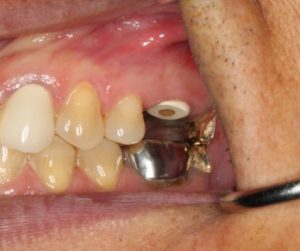

Preoperative 3D imaging is helpful in visualizing the patient’s anatomy and screening the ideal candidate. Since there is limited bone available, a dental implant with aggressive threading is important to obtain good primary stability. Typically, the socket is larger than the diameter of the dental implant and a bone graft is required to fill the space. A large stock, or customized healing abutment, can then be used to contain the bone graft and allow for ideal soft tissue healing.

Immediate implant placement in extraction sockets is a predictable procedure with favorable results. Immediate placement provides a tremendous benefit for patients as it eliminates the need for a second surgery and significantly reduces treatment time. With immediate placement patients can receive their new implant restoration four months after extraction, compared to the traditional eight month waiting period with two or more surgeries.